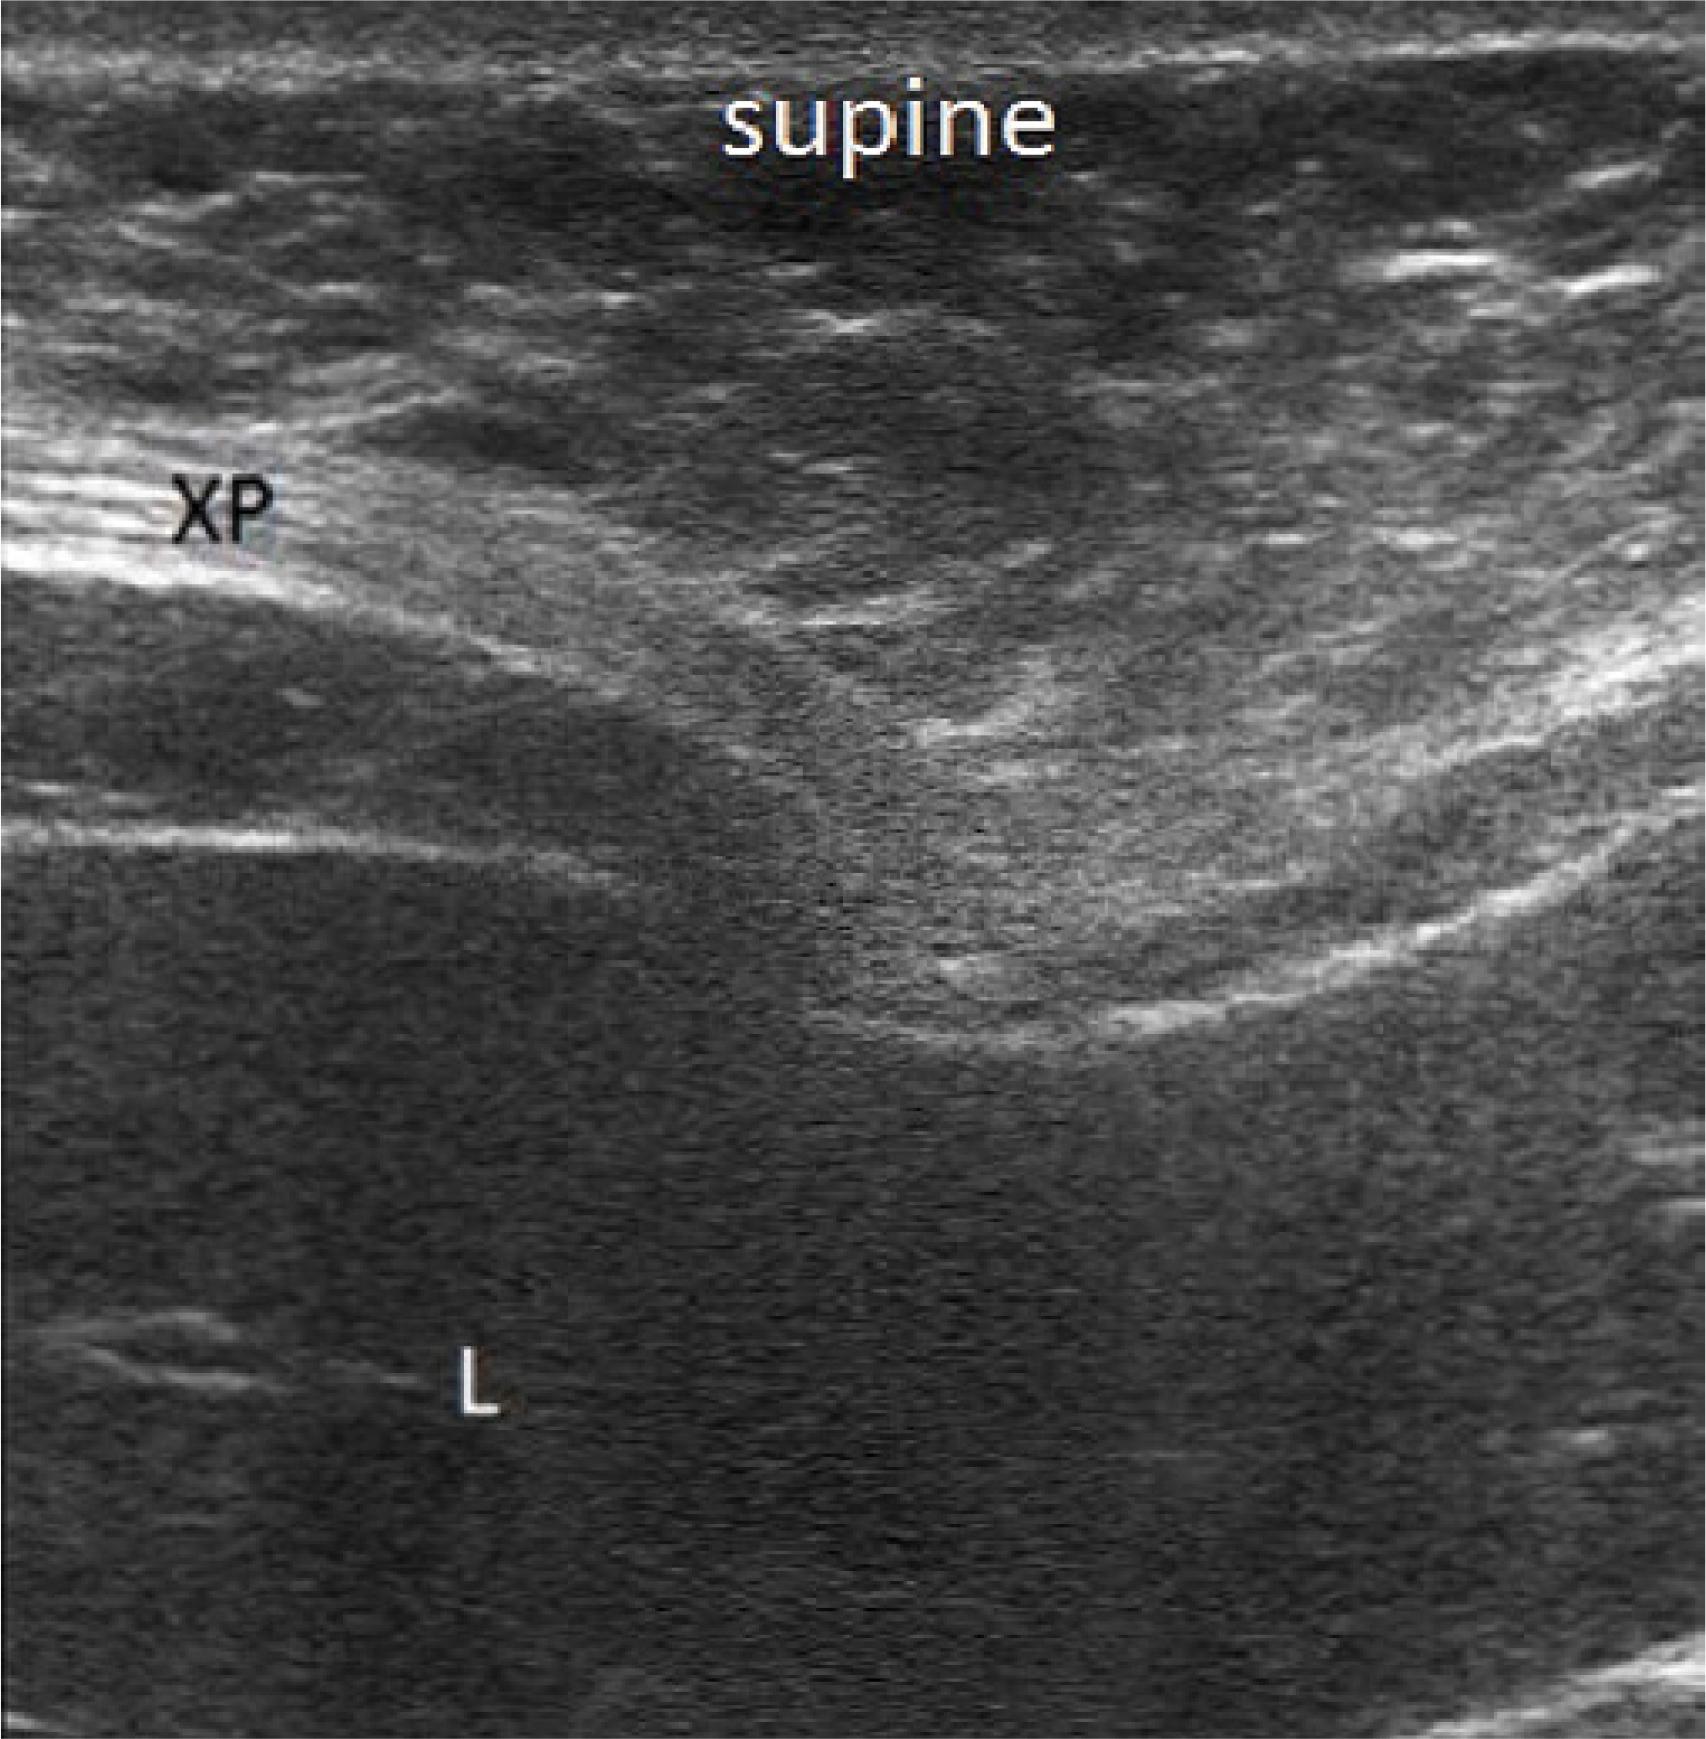

Fig. 4